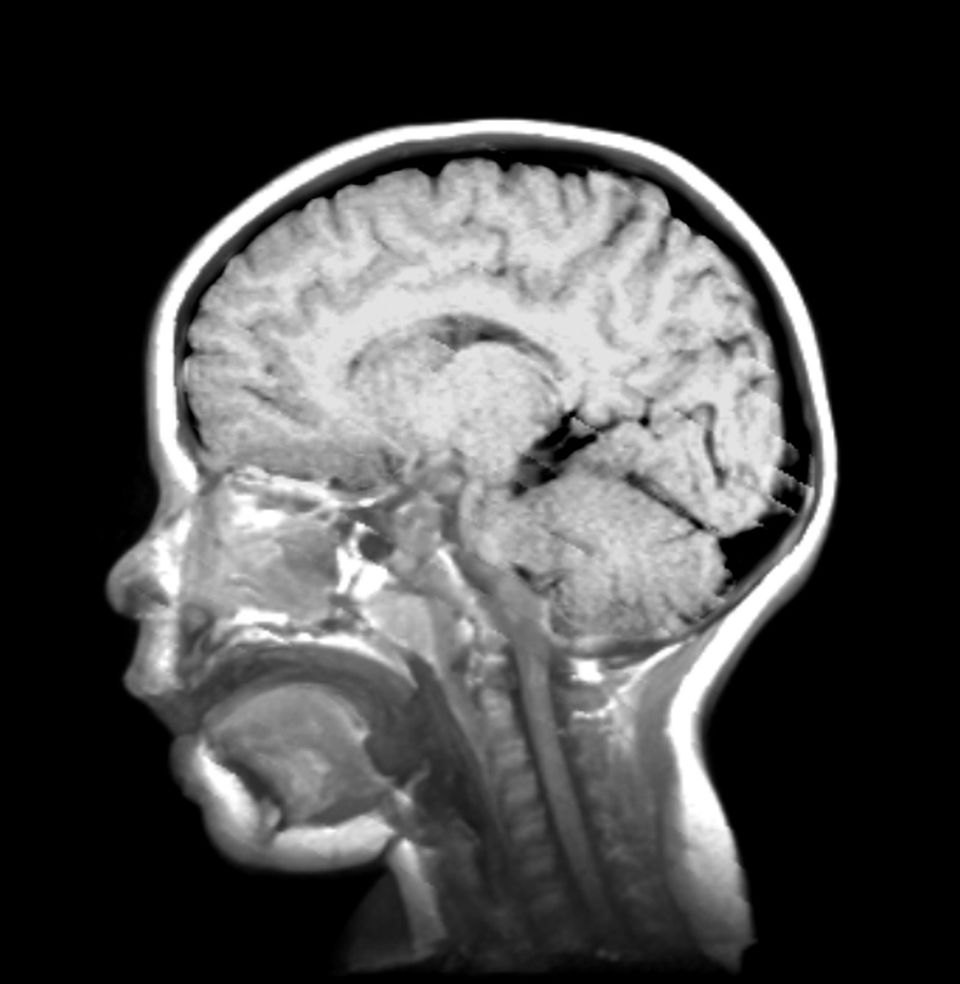

Wo sind unsere Erinnerungen geblieben? Diese Frage stellen sich an der Yale-Universität Forschende am Institut für kognitive Psychologie und Neurowissenschaften. Statt vom Vergessen sprechen sie von infantiler Amnesie, statt angestrengt in den eigenen Erinnerungen zu kramen, nutzen sie funktionelle Magnetresonanztomografie, kurz fMRT, um die Hirnströme von Säuglingen zu vermessen. Solche Untersuchungen an Babys durchzuführen, stellt die Wissenschaftlerinnen vor einige Herausforderungen.

Die Forschenden gingen lange Zeit davon aus, dass unsere Gehirne in den ersten Lebensjahren schlicht nicht weit genug entwickelt sind, um derartige Erinnerungen zu speichern. Zuständig dafür, das weiß die Neurowissenschaft dank fMRT-Untersuchungen an Erwachsenen: der Hippocampus – ein Teil unseres Gehirns, der sich noch bis weit in unsere Jugend hinein ausbildet.

Das Ergebnis der fMRT-Messungen: Je länger sich die Säuglinge ein mutmaßlich bekanntes Bild ansahen, je stärker also ihre Erinnerung, desto intensiver war auch die Hirnaktivität in ihrem Hippocampus. Dabei leuchtete gerade jener Bereich auf, der auch bei Erwachsenen für episodische Erinnerungen zuständig ist.